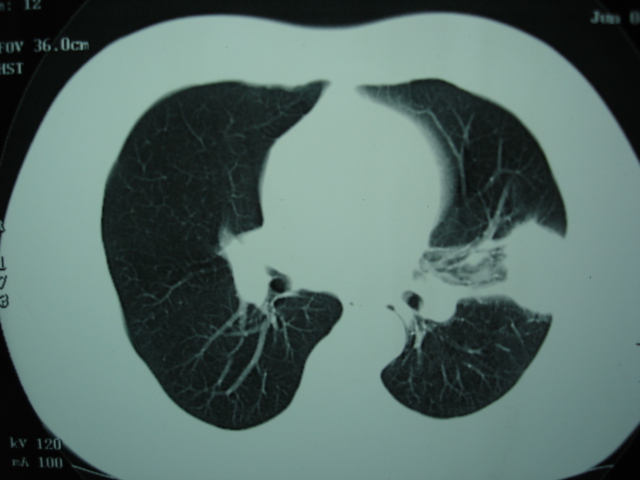

2009.6.4 2009.6.7 2009.8.21

第二次ct2009.6.7 住院后ect未见异常,查痰(阴性)大量抗菌素抗炎一个月后病灶明显变小,7月5号出院后回家后口服抗菌素45天